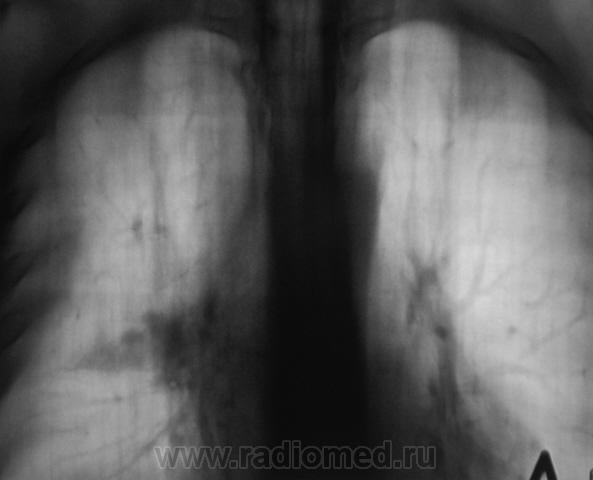

Скорее всего ателктаз 6 сегмента. Он явно объемно уменьшен, да и на качественной боковой можно найти ампутацию бронха, а на прямой томо - не все в поряде с корнем. Валентин Львович, доброе утро! Вы будете не собой, если не выложите серию боковых томограмм.

Вообще-то, объёмного уменьшения нижней доли справа нет ( все сосуды на месте)-вероятно, это не ателектаз.